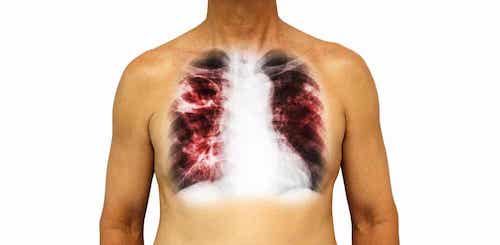

2. La tuberculose

Il s’agit de l’une des dix principales causes de décès dans le monde. Elle a touché 10 millions de personnes en 2018, dont 1,5 million sont décédées, selon les données fournies par l’Organisation mondiale de la santé (OMS).

Les bactéries qui causent cette maladie – Mycobacterium tuberculosis – sont devenues très résistantes aux traitements conventionnels, ce qui représente une crise de santé publique, ainsi qu’une menace pour la sécurité sanitaire. Malgré ces données très négatives, chaque année, l’incidence de cette maladie est réduite d’environ 2 %.

La tuberculose se transmet par l’air, et la personne infectée peut ou non développer des symptômes. De toutes les personnes infectées, seulement 10 % sont symptomatiques. Parmi les signes les plus courants, figurent les suivants :

- Inconfort général

- État fébrile

- Toux et expectoration

- Transpiration excessive